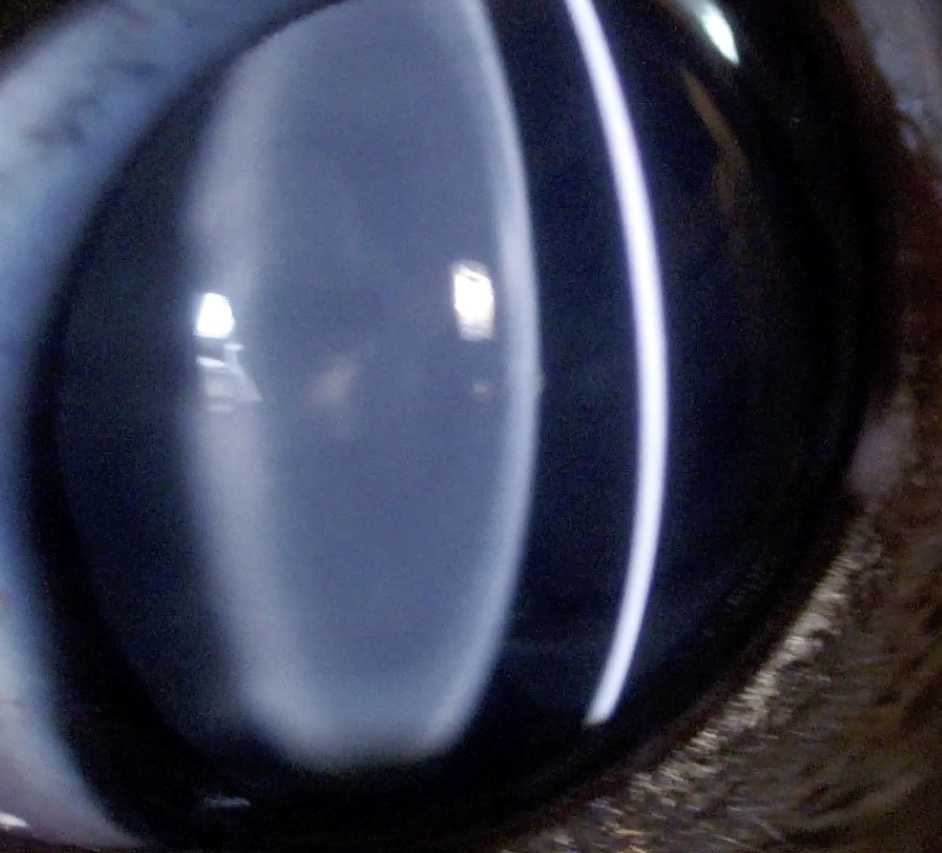

スリットランプで診てみよう

白内障 検査

一般診療で聴診や検温するように、眼科診療はスリットランプ(細隙顕微鏡)検査から始めます。

細い光を斜めに当てて角膜表面を診察します。スリットランプで角膜断層像を診察することにより、角膜表層(上皮)、中間層(実質)、深層(内皮)を診察します。